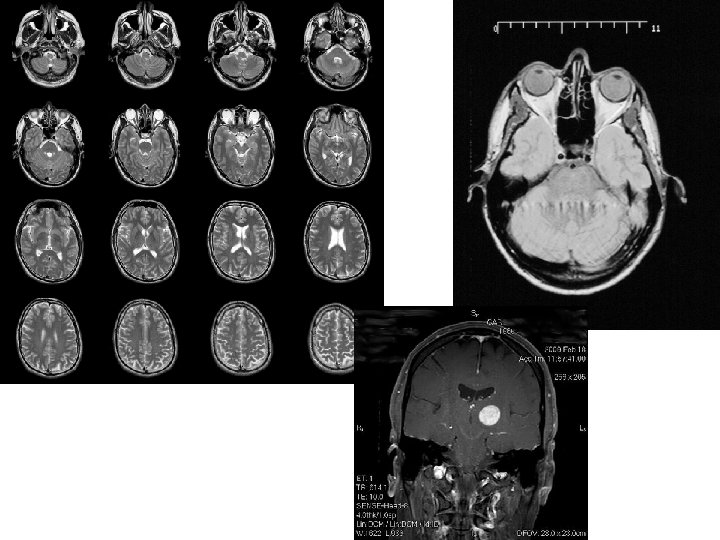

MRI • What do we use the scan for? – Damage to really specific parts • Strengths/limitations – Strengths: three dimensional pictures • Allows us to see more structure – Limitations: • Safety (metal? ) but it is limited on x-ray radiation • Does not show activity

• Corkin et al (1997) – MRI Scan – Parts missing • Pieces of temporal lobe (hearing and language) • Limbic System – Hippocampus (memory) – Amygdala (emotion and fear) – Damage wasn’t as severe as Milner thought

Physiology of PTSD • Decrease in the size of the hippocampus – Connects and organizes memories – Stanford University (2009) • children with PTSD • Used (MRI) • Researchers found that children with PTSD symptoms also tended to have a poorly functioning hippocampus. – Yale University (1995) • Vietnam Veterans with memory problems • 8 percent reduction in the size of the right hippocampus, while other portions of the brain retained their size. • Over reactive amygdala

Rauch et al. , 1998 • Method: Case Study • Hypothesis: Amygdala and Hippocampus are impacted by PTSD • Procedure: PET and MRI studies • Results – Veterans with PTSD demonstrate increased right amygdala activity when exposed to combat movies. – Both male combat veterans and women survivors of childhood sexual abuse with PTSD have lower hippocampal volumes. • Implications – Decreased volume of the hippocampus correlated with trauma exposure or memory deficits.

Harvard Medical School, 2002 • Case Study • AIM: relationship between hippocampi and PTSD • Procedure – MRI bran imaging – pairs of identical twins • one twin served in Vietnam and the other did not. • Results: – The veterans with PTSD did in fact have smaller hippocampi than the veterans who did not. – Brothers of the veterans with PTSD also had smaller than average hippocampi. • Implications – Smaller than average hippocampus is not the result of PTSD, but a risk factor for developing it.